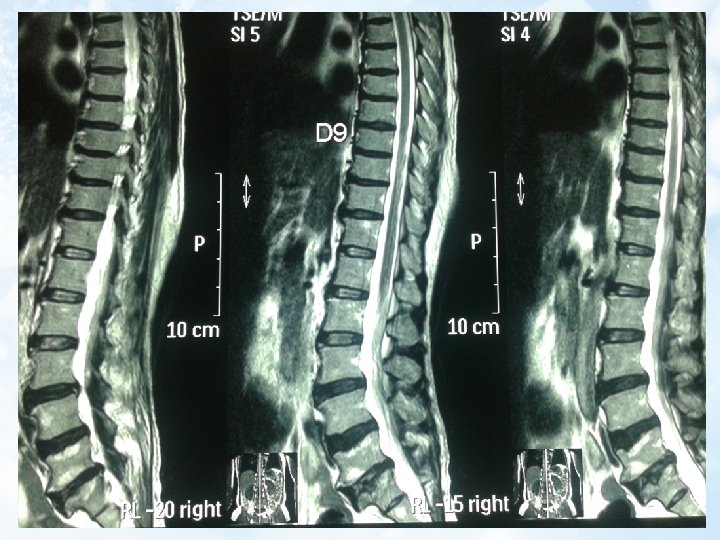

6. MRI Thoái hóa đốt sống thắt lưng và đĩa đệm L 3/4, L 4/5, L 5/S 1 Thoát vị đĩa đệm L 5/S 1 trung tâm chèn ép bao màng cứng và chèn rễ thần kinh cũng mức 2 bên Thoát vị Schmorl S 1 Tủy bám thấp, theo dõi viêm tủy cắt ngang D 11 L 2

b. Chẩn đoán phân biệt tổn thương do chèn ép hay do viêm: -Sự giảm tín hiệu xung T 1 và tăng tín hiệu xung T 2 trên MRI (hình ảnh) -Dựa trên lâm sàng Dấu chứng Khởi đầu Triệu chứng bắt đầu Chèn ép tủy Từ từ O Đau kiểu rễ, diện chèn X ép giảm mất cảm giác Viêm tủy Đột ngột Nhiễm trùng X O Diễn biến Liệt co cứng nhiều O Liệt mềm-cứng X Dịch não tủy Phân ly đạm tế bào O Protein và tế bào tăng O -Trên MRI đồng thời có hình ảnh tăng tín hiệu đặc trưng cho viêm tủy đồng thời cũng có sự chèn ép rễ L 5/S 1 do thoát vị đĩa đệm. Tuy nhiên với sự chèn ép rễ như vậy không thể khiến bệnh nhân liệt hoàn toàn về cả cảm giác, vận động và phản xạ tự động được.

d. Chẩn đoán viêm tủy cắt ngang cấp nguyên phát(Có: X) Tiêu chuẩn chẩn đoán Rối loạn vận động, cảm giác hoặc tự động của tủy sống Triệu chứng cả 2 bên (không nhất thiết đối xứng Clearly define sensory level? Loại trừ nguyên nhân chèn ép tủy bằng chẩn đoán hình ảnh X Dấu chứng viêm (tăng lympho dịch não tủy/tăng Ig. G/tăng gadolinium MRI) Tiến triển tới năng nhất trong vòng 4 giờ đến 21 ngày • Tiêu chuẩn loại trừ Tiền sử tia xạ xương sống trong vòng 10 năm qua X Lâm sàng ít phù hợp với huyết khối động mạch trước cột sống O X Huyết thanh học hoặc lâm sàng của bệnh mô liên kết (SLE, Behcet, Sjogren, Sarcoidosis. . . ) X Lâm sàng hoặc labo biểu hiện của Syphilis, Lyme, HIV, HTLV 1, Mycoplasma và bệnh virus khác X Bất thường MRI gợi ý xơ cứng rải rác O O Tiền sử lâm sàng viêm dây thần kinh thị Chú ý: tiêu chuẩn loại trừ nguyên nhân chèn ép tủy là có vì, khám lâm sàng cho thấy tổn thương đến tận đốt tủy T 11, T 12 (do mất cảm giác trên nếp lằn bẹn một ít). Nên không thể nào là do nguyên nhân chèn ép vì nó chèn ở đoạn đốt sống L 5, S 1 tương ứng với đốt tủy cùng được. ? O O ?

e. Chẩn đoán thể: (Theo Transverse Myelitis Association) Thể Tiêu chuẩn lâm sàng Viêm tủy cắt ngang một Rối loạn chức năng tủy phần cấp sống không đối xứng Tiêu chuẩn MRI <3 đốt sống Viêm tủy cắt ngang hoàn Rối loạn hoàn toàn vùng <3 đốt sống toàn cấp phía dưới tổn thương Viêm tủy cắt ngang rộng Rối loạn hoàn toàn hoặc > hoặc = 3 đốt sống theo chiều dọc không hoàn toàn • Như vậy theo MRI: có dấu tổn thương kiểu viêm từ T 11 -L 2 (4 đốt sống) • Chẩn đoán thể: Viêm tủy cắt ngang rộng theo chiều dọc